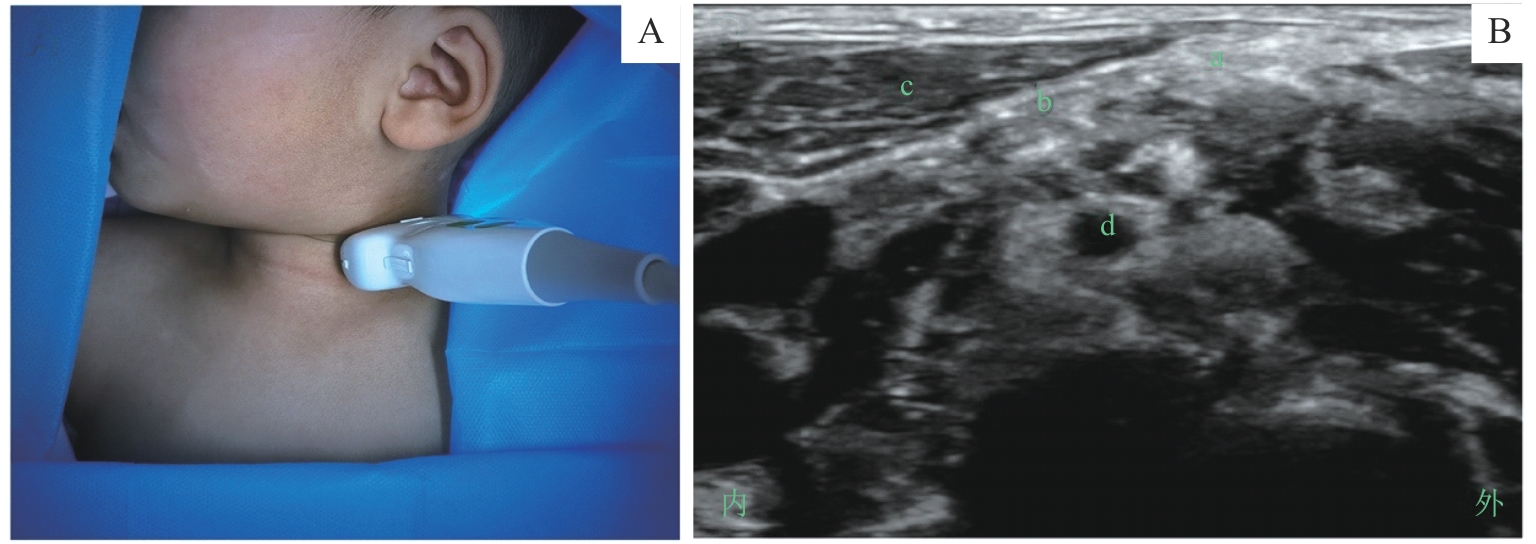

图7 颈浅丛阻滞的超声定位和影像Note: A. 超声探头体表扫描定位/Surface scanning for ultrasound probe positioning. B. 探头处于图A位置时的颈浅丛超声影像/Ultrasound image of the superficial cervical plexus obtained with the probe positioned as shown in figure A. a—颈浅丛/superficial cervical plexus; b—颈深筋膜/deep cervical fascia; c—胸锁乳突肌/sternocleidomastoid muscle; d—C5神经根/C5-nerve root.

Fig 7 Ultrasound positioning and imaging of the superficial cervical plexus block